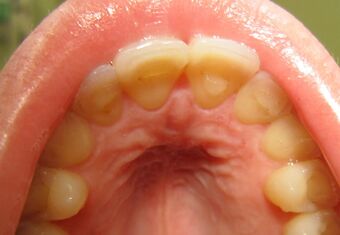

Loss of enamel (acid erosion) from the inside of the upper front teeth as a result of bulimia

The erosion on the lower teeth was caused by bulimia. For comparison, the upper teeth were restored with porcelain veneers.[13]